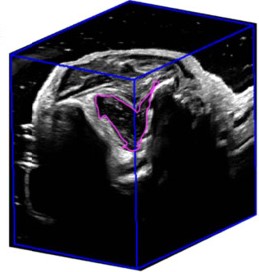

NovaSonix Healthcare is transforming musculoskeletal (MSK) imaging with MSKNovaVue™, an attachment that turns any standard ultrasound machine into a real‑time 3‑dimensional scanner. Designed to work with any commercially available ultrasound machine, MSKNovaVue™ automatically captures full 3D images in seconds, while on‑board AI algorithms quantify disease biomarkers such as cartilage thickness and joint inflammation. By capturing true volumetric and dynamic data, MSKNovaVue™ delivers MRI‑like insight at a fraction of the cost and without the long wait times that plague today’s patients and clinicians.

Monitoring

3DUS allows for:

- Precise measurement of treatment effectiveness

- Monitoring of progression of disease

- Monitoring of treatment response